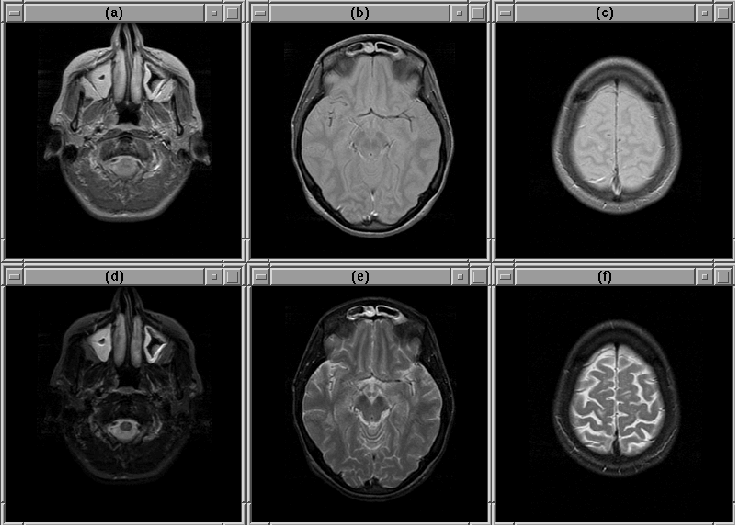

Figure 8.1 shows three slices selected from Data Set 1. The extreme slices (particularly the lowest slice) exhibit considerable partial volume effect resulting in a non-distinct intracranial boundary. The boundary is difficult to detect accurately in these slices. Except for intensity variation due to RF inhomogeneity, other slices in the volume contain no remarkable features.

Figure 8.1: Selected slices from MRI Data Set 1. (Top) PD-weighted. (Bottom) T2-weighted. (a), (d) Slice 1. (b), (e) Slice 14. (c), (f) Slice 27.